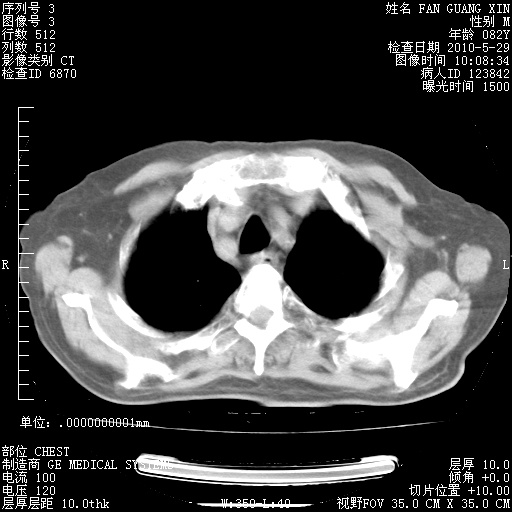

还需要哪些辅助检查?我们医院排除真菌感染没有任何检验方法,胸片好像能够排除肺部真菌感染。